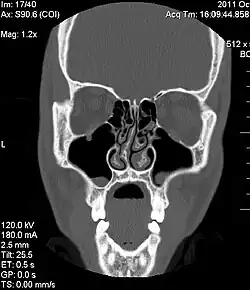

Diagnóstico

O desvio de septo nasal é a causa mais comum de obstrução nasal.[7] Uma história de trauma no nariz é frequentemente presente, incluindo trauma do processo de nascimento ou microfraturas.[7] Um profissional médico, como um otorrinolaringologista (médico dos ouvidos, nariz e garganta), tipicamente faz o diagnóstico depois de tirar uma história detalhada do paciente e performar um exame físico.[7] Exames de imagem do nariz às vezes são usados para auxílio diagnóstico.[7]